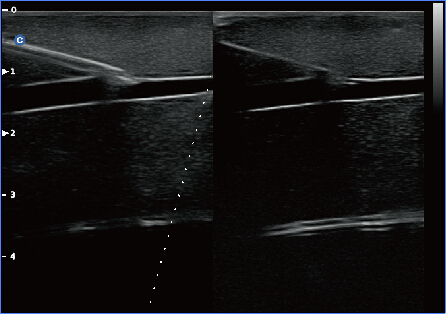

Super Needle

Con Super Needle, los médicos pueden ver la aguja dentro del tejido más claramente durante procedimientos médicos. Ángulo de la aguja hasta ±30 °